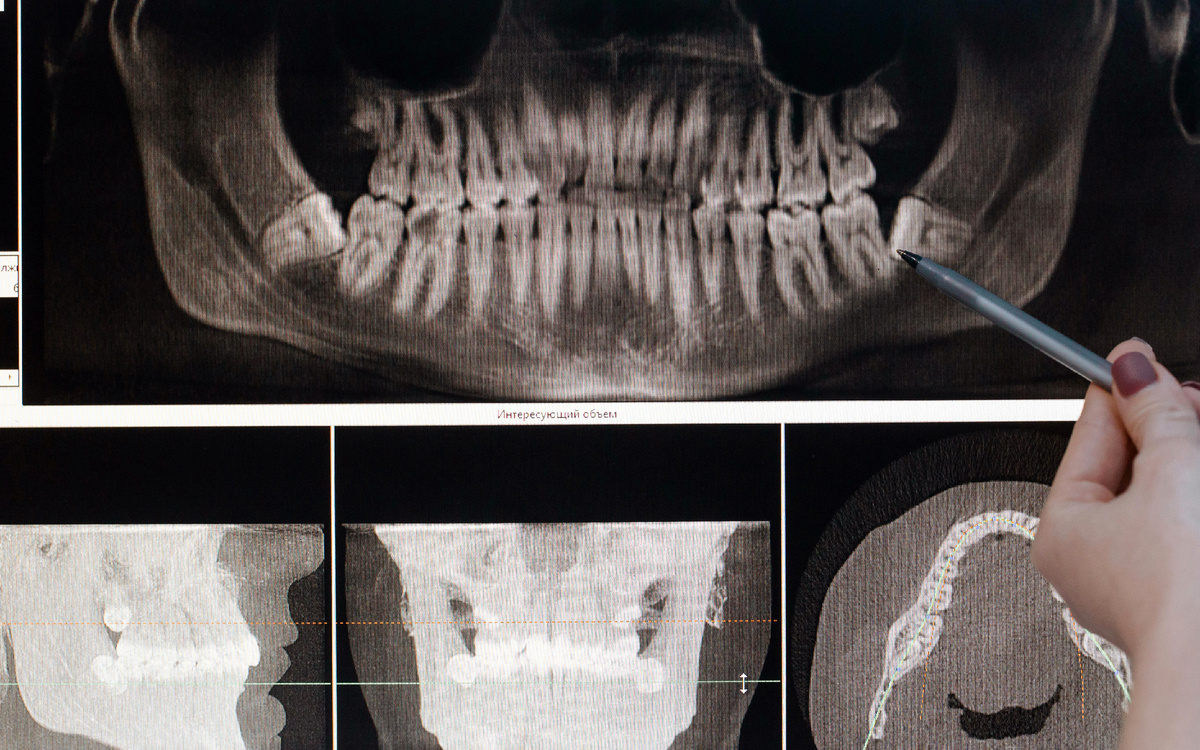

Зубы мудрости — последние в ряду моляров, которые обычно прорезываются в возрасте от 17 до 25 лет. Но вместо того, чтобы служить человеку, они часто становятся источником проблем. Почему же стоматологи рекомендуют их удалять рассказали в этой статье. Современная анатомия человека отличается от строения наших далеких предков. Челюсти стали меньше из-за изменения рациона и способов приготовления пищи. В результате зубам мудрости часто не хватает места для правильного роста. Это приводит к их смещению, деформации или даже врастанию в соседние зубы. Зубы мудрости прорезываются медленно и частично, оставляя ткани десны поврежденными или прикрытыми "капюшоном". Это создает идеальные условия для размножения бактерий. В результате развивается воспаление десен — перикоронарит, которое может сопровождаться болью, отеком и даже повышением температуры. Когда зуб мудрости растет под наклоном, он давит на корни соседних зубов. Это не только причиняет боль, но и может стать причиной их повреждения.

Современная анатомия человека отличается от строения наших далеких предков. Челюсти стали меньше из-за изменения рациона и способов приготовления пищи. В результате зубам мудрости часто не хватает места для правильного роста. Это приводит к их смещению, деформации или даже врастанию в соседние зубы.

Когда зуб мудрости растет под наклоном, он давит на корни соседних зубов. Это не только причиняет боль, но и может стать причиной их повреждения. Если проблему не решить вовремя, зуб рядом с "мудрецом" может пострадать настолько, что тоже потребует лечения или удаления.